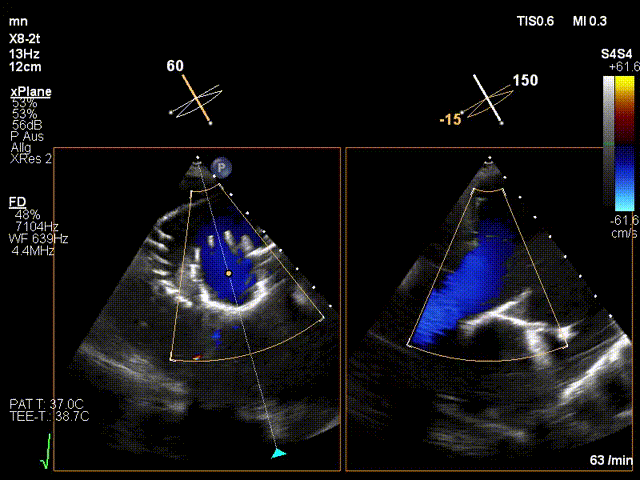

手術(shù)在全麻狀態(tài)下進(jìn)行。在加拿大圣保羅醫(yī)院的Anson Cheung教授的指導(dǎo)參與下,術(shù)者采用經(jīng)右側(cè)頸靜脈入路的方式將輸送器送入患者心臟內(nèi),在TEE及DSA引導(dǎo)下調(diào)整輸送器頭端角度,使得輸送器與三尖瓣瓣環(huán)平面垂直。在輸送器進(jìn)入右心室后釋放室間隔錨定裝置,而后釋放瓣葉夾持件(2個耳片結(jié)構(gòu))成垂直狀態(tài)。在TEE及DSA確定夾持件固定至三尖瓣葉根部且位于右室側(cè)后釋放人工瓣心房側(cè)盤片。隨后調(diào)整瓣膜同軸性以及室間隔錨定件位置(貼合室間隔),前推藏針管并固定,進(jìn)而釋放室間隔錨定裝置,并再次確認(rèn)瓣膜位置、穩(wěn)定性及同軸性,合攏輸送鞘后撤出輸送器,完成LuX-Valve Plus人工三尖瓣瓣膜的植入。

LuX-Valve Plus經(jīng)血管三尖瓣置換系統(tǒng)本次“出海”圓滿完成,術(shù)后Jörg Hausleiter教授對LuX-Valve Plus經(jīng)血管三尖瓣置換系統(tǒng)的器械性能和治療效果大為稱贊,認(rèn)為LuX-Valve Plus的手術(shù)體驗(yàn)非常好。術(shù)后即刻超聲顯示三尖瓣反流消失,血流動力學(xué)改善顯著,患者恢復(fù)快。Anson Cheung教授也肯定了LuX-Valve Plus術(shù)中操作的便捷性,認(rèn)為LuX-Valve Plus容錯率高,對術(shù)中影像的依賴較小,后期希望可以更多的應(yīng)用LuX-Valve Plus三尖瓣置換系統(tǒng)于臨床實(shí)踐,讓更多的三尖瓣重度反流患者盡早獲益,改善預(yù)后。